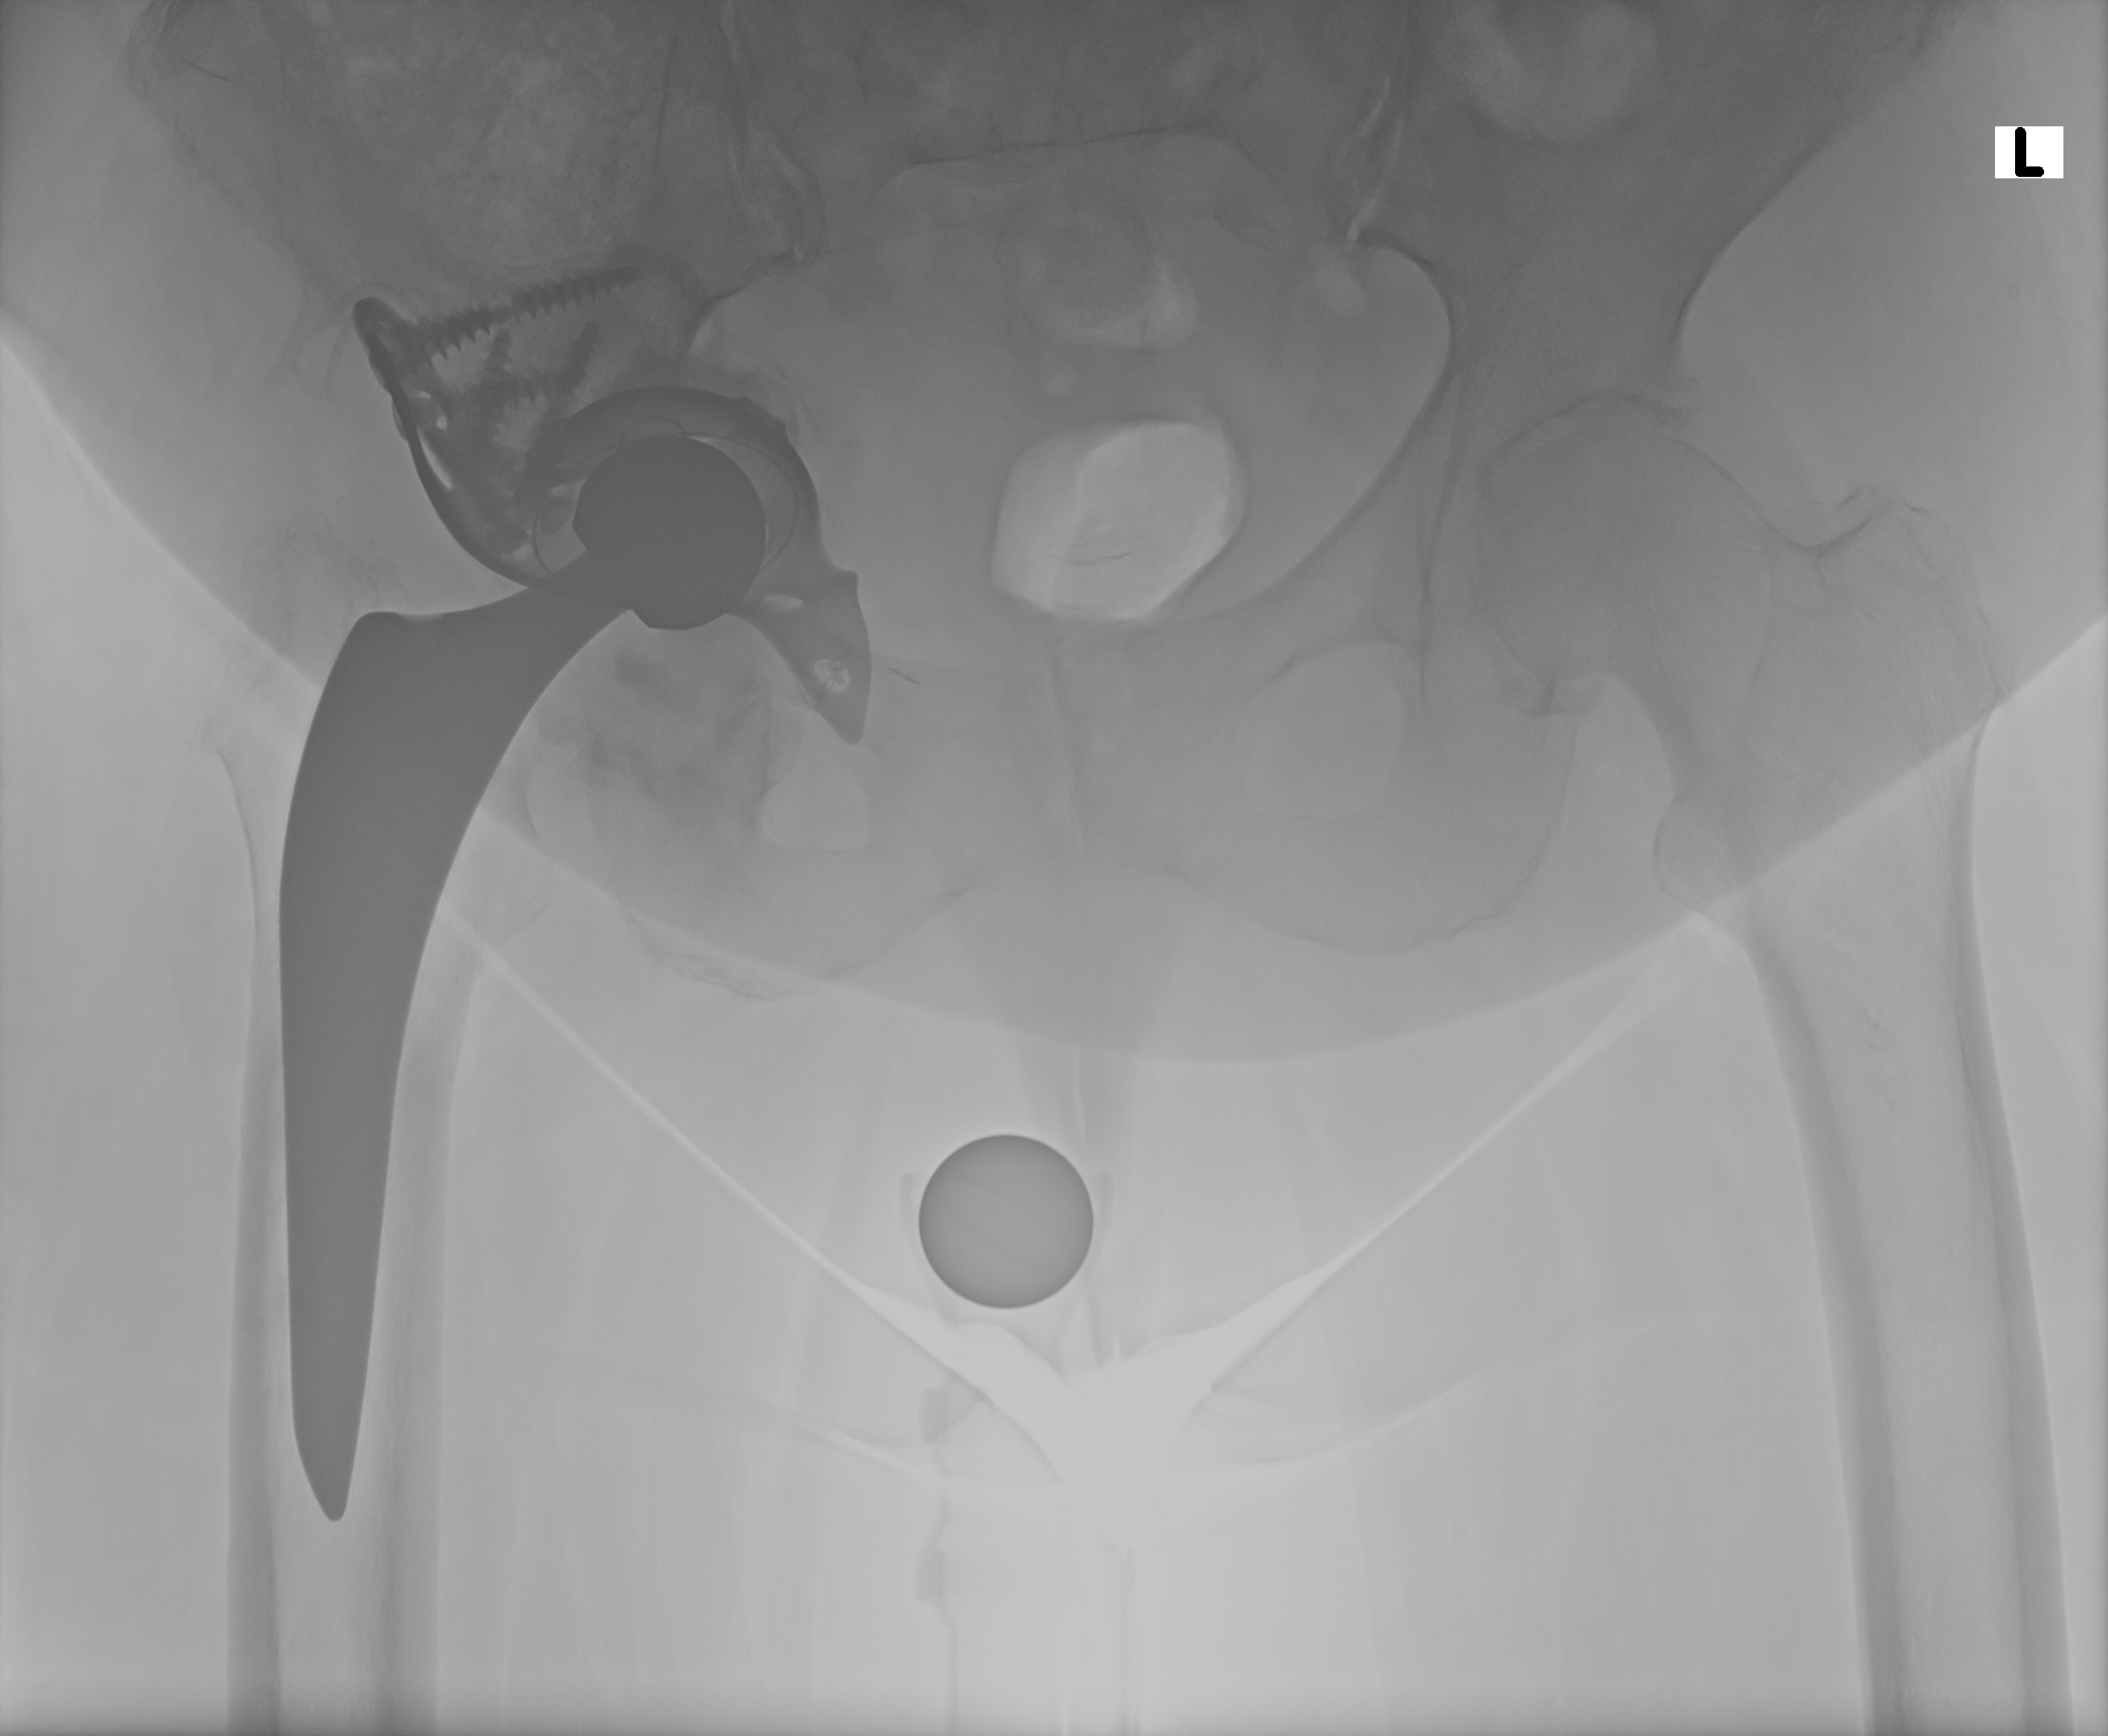

07.10.2024 - Korrekt

Röntgen Oktober 2024

Prothesenkopf sitzt korrekt in der Pfanne

07.10.2024 - Prothese korrekt

Becken 2024

Prothesenkopf sitzt in der Pfanne

07.10.2024

Röntgen Becken (PELVIS)

2 Aufnahmen | 3040x2466 px | 6.9 MB

PELVIS Becken

DICOM

Kontroll-Röntgen - Prothese noch korrekt positioniert